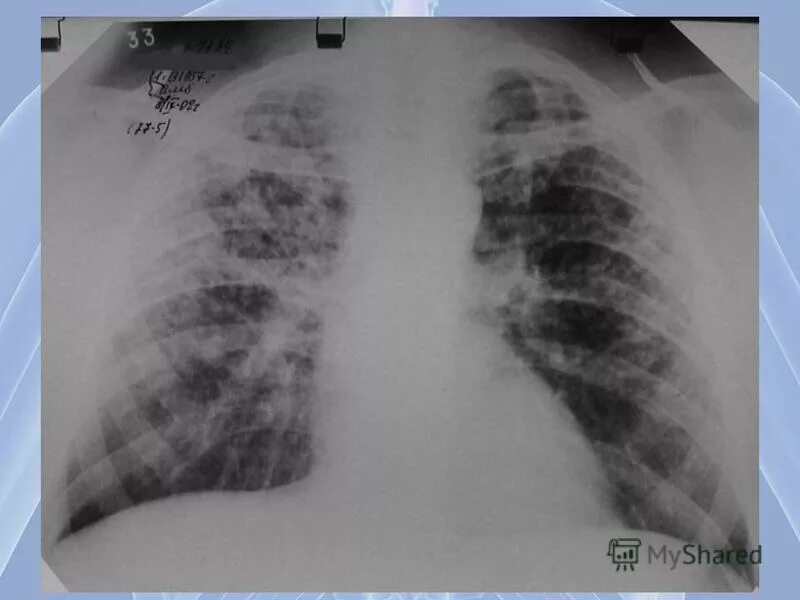

Метастазы в средостении легких